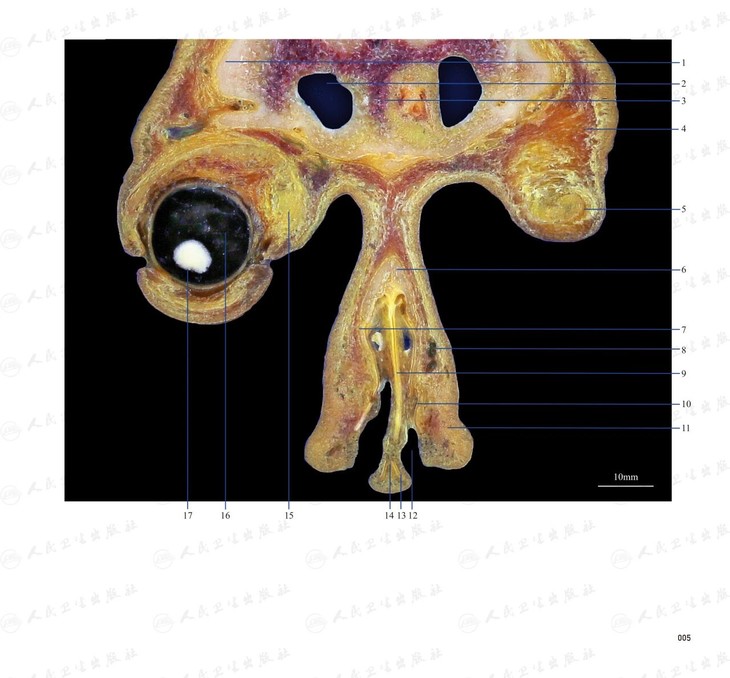

本书从数据集每隔1.2mm选取一幅图像,截取眼、耳、鼻及毗邻颅底的局部区域图像,共112幅图像。同时配以相应部位的CT图像对照。本书特色是断层解剖图利用数字图像处理技术优势,放大并清晰展示眼、耳、鼻及毗邻颅底断面的局部区域结构,组织色泽真实,甚至能够清晰显示肌肉纹理、筋膜纹路等细节结构,图像质量高于美国同类断层解剖彩色图的图像质量。对眼科、耳鼻咽喉科和神经内外科医生理解相关解剖结构有较大帮助。